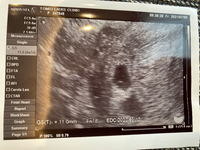

胎嚢の平均的な大きさ 4週目:まだ見えない 5週目:1673mm 6週目:2394mm 7週目:3011mm 8週目:43mm 9週目:5196mm 上記は三重大学医学部の資料による数値です。 胎嚢は妊娠週数が進むにつれて大きくなっていきますが、上記数値はおおよその胎嚢の大き 先生には5週目ぐらいねって言われたんですが、 ここで見てると5週で5ミリって小さいですよね?? ちなみに基礎体温はつけておらず、生理も不順なので 今何週なのかは胎嚢の大きさを見て決めましょうと言われました。 受精後16日目(妊娠4週2日):約15mm 受精後17日目(妊娠4週3日):約24mm 受精後18日目(妊娠4週4日):約33mm 受精後19日目(妊娠4週5日):約442mm 受精後日目(妊娠4週6日):約535mm 受精後21日目(妊娠5週0日):約628mm 尿中HCG反応が陽性(妊娠検査薬が陽性)になってから2日以上後、 胎嚢が確認出来ない場合は、超早期流産経過中と考えられ

妊娠5週ごろの胎嚢の大きさは、直径約1cm。 また、胎嚢の中に卵黄嚢(らんおうのう)というリングのような組織も確認できるようになります。 赤ちゃんは卵黄嚢から栄養を受け取って成長していきます。 胎嚢は1日に1mmほど大きくなり、その大きさは、「妊娠週数-4」という関係式が目安になります。 妊娠6週であれば「6-4=2」ですから、胎嚢の大きさは約2cmと 5週1日の時は、胎嚢確認のみでき胎嚢69ミリ。 今日、胎嚢は117ミリでした。 心拍確認出来てもいい頃だけど出来ないから 一週 妊娠 胎嚢26ミリ、胎芽29ミリって小さいですか? 確定はできませんが妊娠7週0日です。 今日診察に行くと胎嚢が264ミリで胎芽が29ミリ、心拍は確認できず卵黄嚢はあるという感じでした。(胎 質問No

今日病院行ってきました 不安で不安で 心臓飛び出そうなくらい ドキドキで 採血して1時間半くらい待ってて28日周期でくる生理が1週間以上来なかったので、市販の検査薬で調べたところ、陽性の線がビタッとくっきり(笑) その日のうちに産婦人科で検査すると、順調ですとのこと(*^^*) 胎嚢157mmでした! 最終生理日から計算すると、5週3日目です。5週0日の胎嚢の大きさについて 5週0日にエコーにて胎嚢が見えました。エコー写真を2枚貰ったのですが、1枚目の大きさが55ミリ 2枚目が少し拡大された画像で41ミリと記載がありまし

5W2Dで4ミリもあるなんて立派ですよ〜! 胎嚢確認は早くて4週後半で、普通は5週ですよね。 だから4ミリで標準だと思います。 ぜんぜん小さくないですよ。 私は無事に妊娠継続して、今は38週です。5週胎嚢大きさ平均, 胎嚢の確認時期はいつ?平均的な大きさとは 以下は平均値の目安です。 👇。 モチロン、今はとても元気ですよ。 45wに市販の検査薬で陽性反応を確認する• 胎嚢の大きさの平均につい 5週の胎嚢サイズ→10~25mm 6週の胎嚢サイズ→15~30mm 7週の胎嚢サイズ→~37mm 胎嚢サイズの目安については以上。 自分の実際の胎嚢サイズと 照らし合わせてみると、 ※経過が分かりやすいように 心拍確認できるまでの結果を 先に載せてしまいます。

妊娠4週になると見えてくる、「胎嚢」「卵黄嚢」って何? 妊娠5週になると脳や神経、心臓など臓器、それに手足や目、耳の原型もできるってホント? 妊娠6~7週で、心臓の動き出す!? まだ「胎児」と呼んでもらえない妊娠2ヶ月の「胎芽」時代の赤ちゃんのこと、母体のこと。 不妊治療 兆候 妊娠 妊娠5週目(5w4d)に、内診検査にて、ついに胎嚢が確認! 5週の胎嚢サイズの平均は1673mmなので、胎嚢は63ミリで小さい。 。 。 ですが、エコー画像を交えてご紹介します。 (杉山産婦人科で体外受精に挑戦し、二度目の移植で奇跡の陽性判定いただきまし5週で6.2ミリ 6週で12.5ミリ(卵黄嚢はみえる)→流産となりました。 私の中では排卵にずれがない場合(あっても2.3日)は 数日胎嚢の大きさが小さいのは大丈夫として 10日以上遅い、一日一ミリ大きくなるこの時期に 一週間で5ミリ以下しか大きくなっていない場合は あまりよくないかなと思い